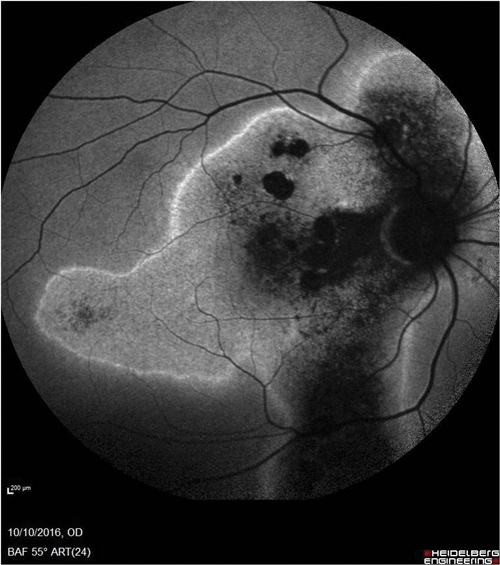

Figure 2: Consequences of chronic CSCR. (Top) Autofluorescence image of the right fundus showing widespread damage and atrophy of the retinal pigment epithelium and a ‘gravitational’ appearance. (Bottom) OCT scan of the same eye showing photoreceptor loss and RPE damage as well as abnormalities in the choroid.

Sight loss is due to photoreceptor damage and atrophy of the retinal pigment epithelium (RPE) (Figure 2). There are many different treatment options for chronic CSCR and no standard guidelines published on treatment protocols [5]. The treatment options range from systemic treatment to photodynamic therapy, as well as argon laser and micropulse laser treatment. Unlike other retinal conditions, anti-VEGF does not appear to be a useful treatment modality.